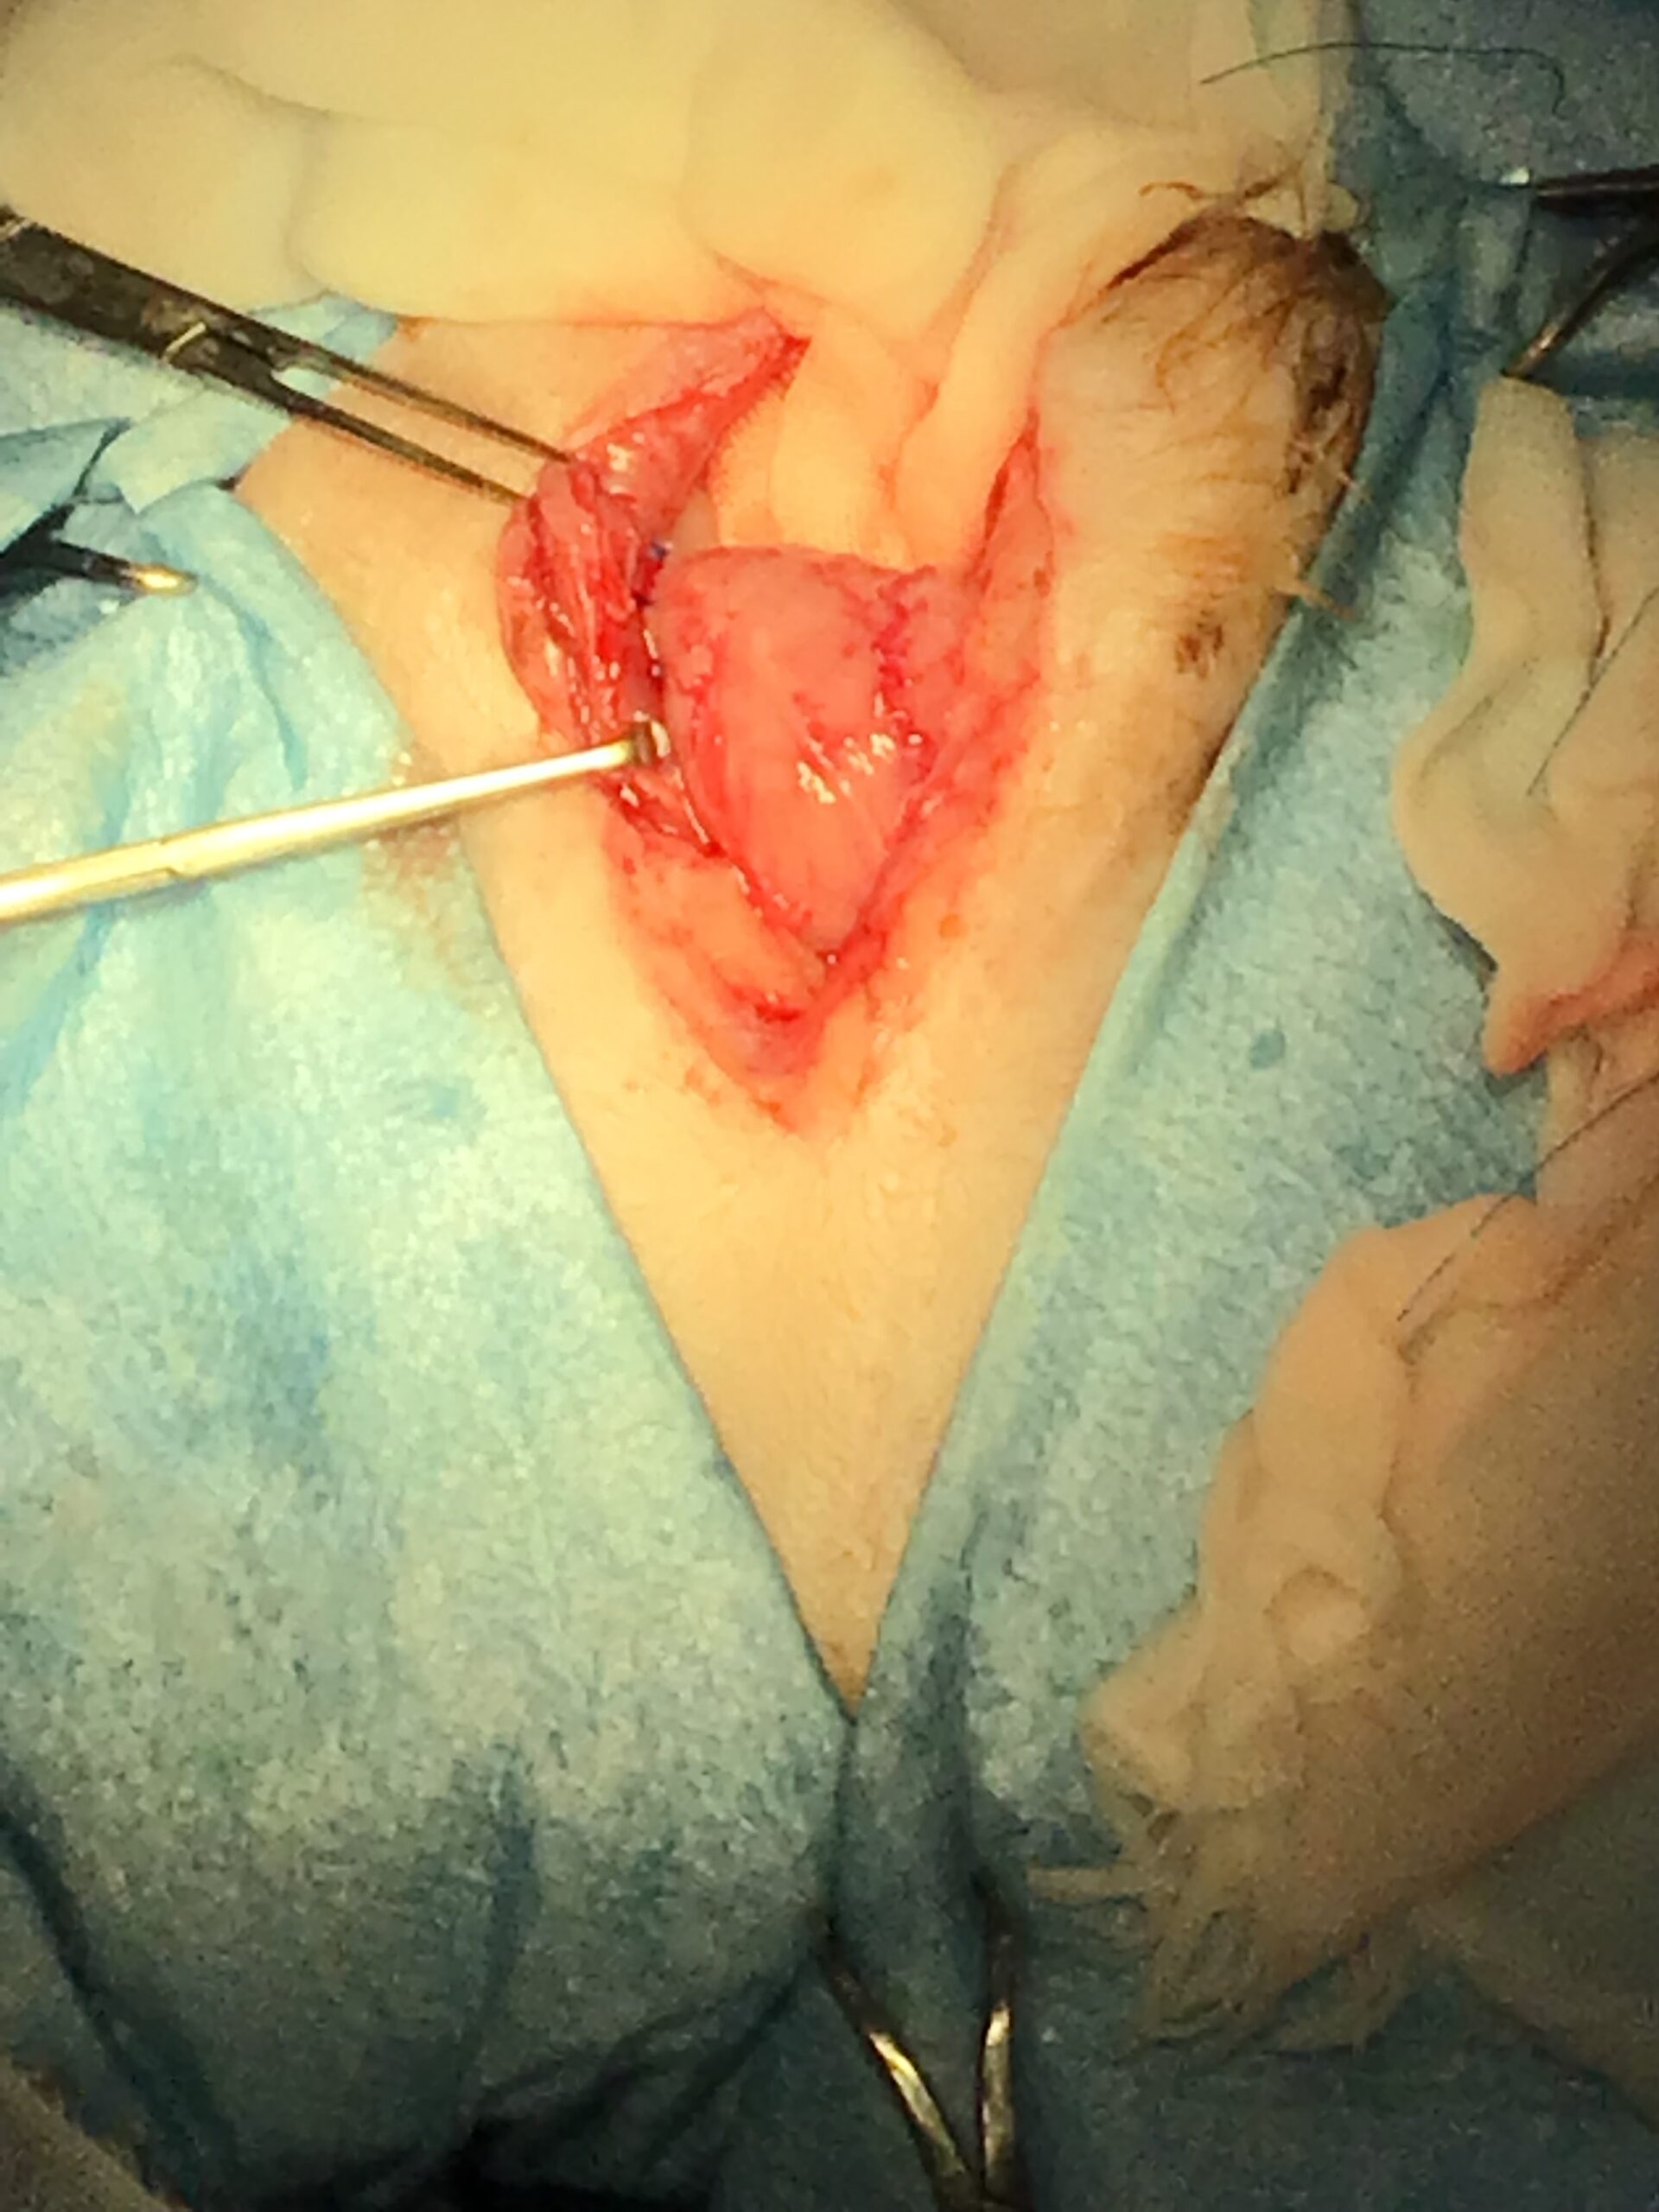

本症例には、時期を分けて2つの大きな外科的介入を行いました。

加えて、会陰ヘルニアの根本的な発症要因となる「前立腺肥大」を退縮させ、将来的な再発リスクを低下させるために、去勢手術も同時に実施しました。

【致死的合併症】メッシュ縫合時に坐骨神経を巻き込んだ場合、術直後から後肢の永久的な神経麻痺(ナックリング)が生じ、直ちに再手術が必要です。また、メッシュへの重度感染や、直腸・前立腺の損傷による化膿性腹膜炎は致死的となります。

This post details our surgical and medical approach to a complex case involving recurrent severe perineal hernia and a malignant liver lymphoma in a senior dog. We emphasize the grim reality of untreated conditions and the severe risks of anesthesia when underlying heart and respiratory diseases are present. To maximize safety, we exclusively use local infiltration anesthesia. Due to a lack of available autologous tissue, a polypropylene mesh and extensive organ pexy (both colon and bladder fixation to the abdominal wall) were required to prevent fatal urethral obstruction and re-herniation. Additionally, simultaneous castration was performed to shrink the enlarged prostate, a key factor in hernia development, thereby reducing the risk of recurrence. For the liver tumor, given its deep location at the liver base and the high risk of fatal bleeding, we opted for a biopsy which confirmed lymphoma. Unfortunately, the patient’s elevated bilirubin and the family’s preference for a compromised, single-agent chemotherapy protocol led to early drug resistance. We candidly discuss the harsh realities of end-stage cancer—it is a painful decline characterized by severe cachexia and organ failure that palliative care can only partially ease. Furthermore, we outline our strict early discharge policy (1-3 days), the physical limitations of our unstaffed overnight remote monitoring, and our referral policy for highly specialized surgeries. We believe in providing honest, logical medical facts rather than false hope, ensuring families can make fully informed and responsible decisions.